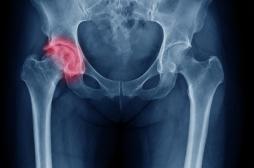

hanche